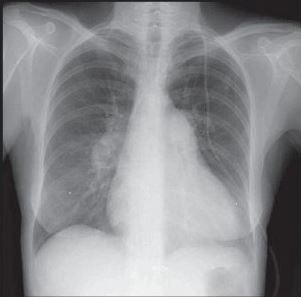

Cardiomegaly and prominent bilateral pulmonary arteries in the hilar areas can be seen in a posteroanterior chest radiograph from a patient with idiopathic pulmonary arterial hypertension. A lateral view also reveals enlarged pulmonary arteries and cardiomegaly without any evidence of congestive heart failure.

Radiographic evidence of longstanding pulmonary hypertension includes enlargement of the central pulmonary arteries with abrupt narrowing of the more distal branches, giving a “pruned tree appearance,” and right ventricular enlargement.

The classic radiographic changes characteristic of RV enlargement include increased transverse diameter of the heart, elevation of the cardiac border on the posteroanterior view, and narrowing or loss of the retrosternal airspace on the lateral projection.

All or some of these findings can be found in patients with idiopathic pulmonary arterial hypertension but lack sensitivity for the diagnosis. There is no correlation between the extent of these abnormalities and the degree of pulmonary hypertension.